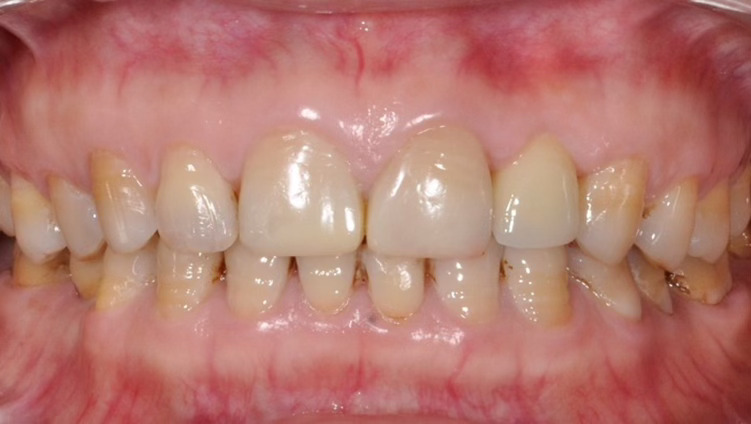

![]() |

| Phục hồi trên implant tại vùng thẩm mỹ như răng thật tại Nha Khoa Như Ngọc (21 Trần quang diệu, Hà Nội). |